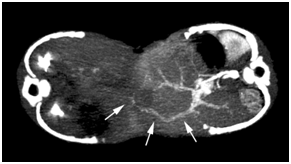

The twins were joined from the lower chest to the umbilicus area. There was no bony connection on conventional x-rays. The hearts and lungs were visible above the conjoined diaphragm. The left- and right-side twins were called Twin A and Twin B, respectively. Barium sulfate was given to Twin A via a nasogastric tube. Serial images showed no evidence of digestive tract communication, and only loops of the upper small bowel of Twin A were seen to project into the abdominal cavity of Twin B through an abdominal wall defect (Figure 1). US showed that the livers of the twins were fused, and the gallbladder and portal vein of Twin B were clearly seen, while those of Twin A were invisible due to intestinal gas interference (not shown). Based on the echo findings, a CT study was designed.

Figure 1 For barium studies, the baby on the right side was given barium sulfate. Barium sulfate was observed only in the intestines of one baby, and no evidence of digestive tract communication was seen.